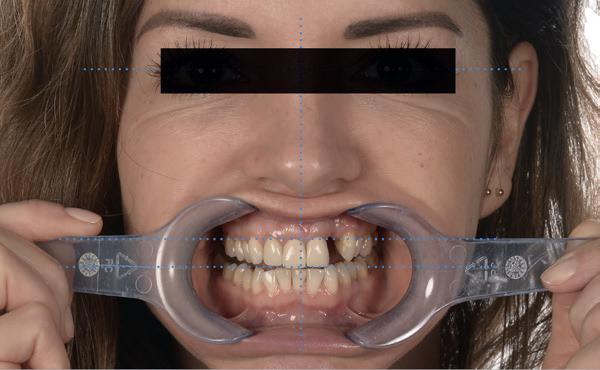

Na de IPP (esthetisch/functionele) analyse blijkt dat de gezichts- en faciale mediaan niet geheel overeenkomen en dat de gingiva lijnen van het bovenfront niet helemaal parallel lopen met de interpupillaire lijn. Na overleg met mevrouw kiest zij ervoor om dit niet orthodontisch te laten corrigeren. Mevrouw

Er wordt een afdruk of een intra-orale scan genomen van de situatie met tijdelijke voorzieningen en de geprepareerde situatie. Ook mag een portretfoto en mondfoto niet ontbreken. Al deze informatie gaat naar het laboratorium zodat de onderstucturen van de restauraties gemaakt kunnen worden (foto 26).